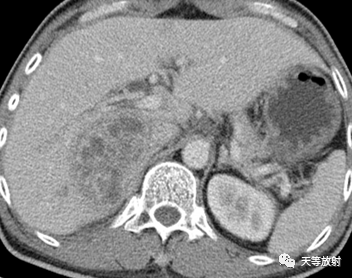

男性,51岁

主 诉:发现肝占位1年余。既往有上消化道出血病史。2022年09月因”1.2型糖尿病伴血糖控制不佳 糖尿病性外周血管病。

肝右叶见不规则团块状稍低密度影,外缘可见水肿带。边缘模糊,增强扫描动脉期呈不均匀强化、以边缘强化为主,门脉期呈边缘持续强化,病变范围4.7*7.5*7.8cm。影像诊断肝脓肿,肝穿刺活检:炎性病灶。

肝脓肿

上图:“周围充血征”表现为脓肿周围肝组织于增强早期的一过性明显强化,反映了脓肿周围肝组织的炎性充血反应.